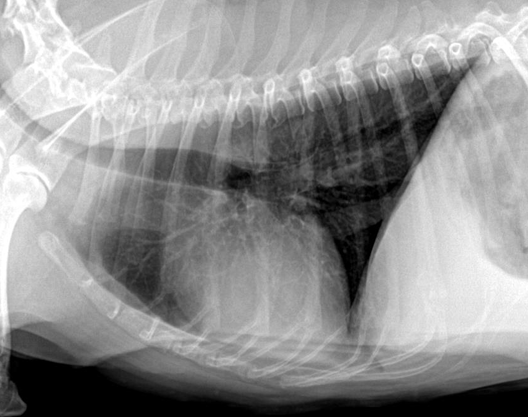

| Inspiration | Expiration |

|---|---|

![]() | ![]() |

| - 폐 부분이 더 opaque (뿌얘보임) | |

| - 횡격막이 더 위로 올라와 심장과 붙어 있음. |